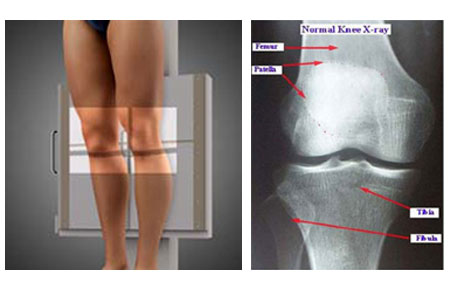

X-rays of the Knee:

These are done to diagnose problems in the bones and or joints

The common types of Knee X-rays a Knee Surgeon would require are

Knee (AP Weight-Bearing View)

Lateral Knee X-rays

Axial View